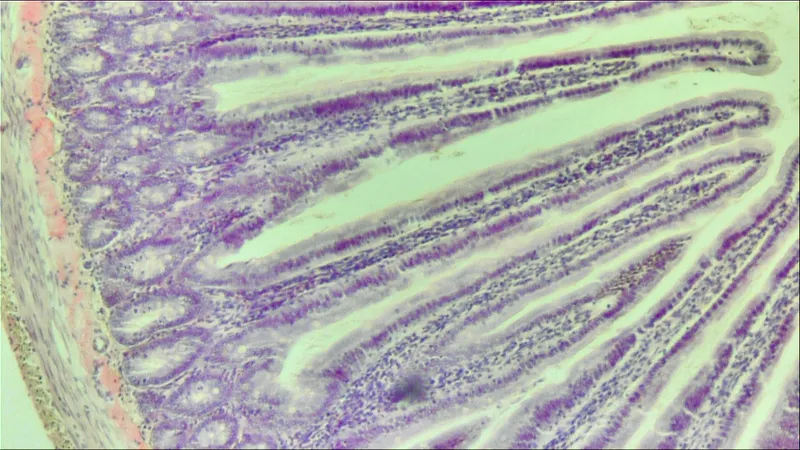

Biosciences host an array of equipment for all of your histology sample preparation needs.

Enabling processing of samples for traditional paraffin embedding and cryosectioning

Histology Equipment

Find out more about our range of histology equipment by selecting the relevant image below.